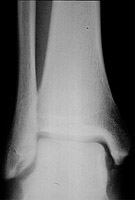

- Click on the image for a larger versionBAP radiograph of the ankle. The fracture is not well seen on this radiograph.